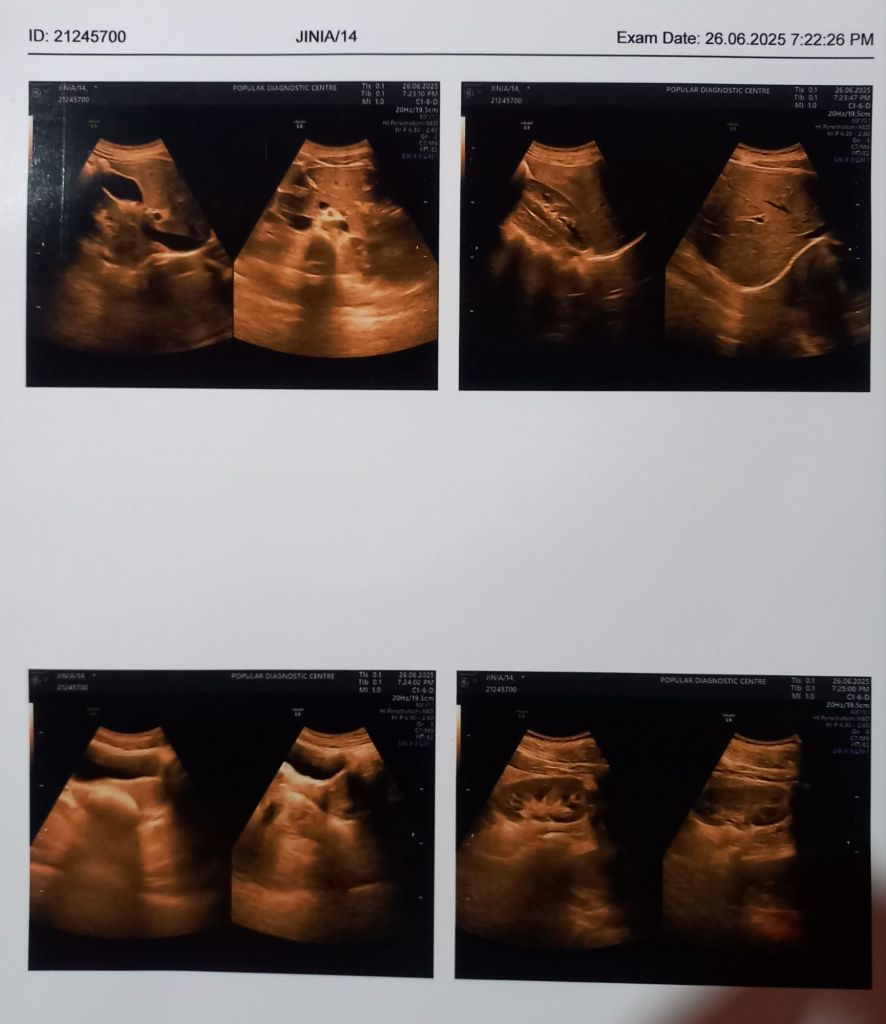

এখন আমাদের হোমিওপ্যাথি ফিলোসফি অনুযায়ী অনেক সময় রোগের উৎপত্তি হয় মন থেকে এটা তার বড় প্রমাণ কারণ হচ্ছে এই Patient এর USG রিপোর্ট অনুযায়ী বিভিন্ন Organ যেমন Liver, Kidney, Spleen, Uterus, Gall bladder, Ovary, Urinary bladder etc. is well বা ভালো। তাহলে প্রশ্ন হচ্ছে কেনো patient এর ব্লাডে এই পরিবর্তনগুলো হোলো? এর উত্তর প্রথমে আমি দিয়েছি আর তা হলো দুশ্চিন্তা। মেয়েটি দুশ্চিন্তার জন্য খাবারও খেতে পারে না। আমি তার চোখে পানি দেখলাম আর দেখলাম একটা সমাধান হীন পারিবারিক সমস্যার দুশ্চিন্তার সমুদ্র যেটা এই মাত্র ১৪ বছর বয়সী মেয়েটাকে শেষ করে দিচ্ছে। আমি তাকে হোমিওপ্যাথির নীতি অনুযায়ী মেডিসিন দিলাম এবং কিছু মেন্টাল সাপোর্ট/এডভাইস বা সাইকোলজিক্যাল সাপোর্ট/এডভাইজ দিলাম। আশা করি ইনশাআল্লাহ সুস্থ হয়ে যাবে, কিন্তু এই পেশেন্টটির সুস্থতা অনেকটা নিজের উপরও ডিপেন্ডে করছে।